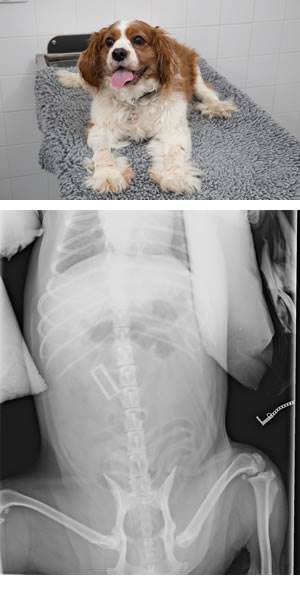

Nine-year-old Cavalier King Charles Spaniel, Cyril, got his paws on a ‘Clarabel’ toy – the famous character from Thomas the Tank Engine at the family home in Torpoint.

The family realised something was wrong when their beloved pet stopped eating and started vomiting. Worried owner Lesley Mellor (40) rushed him in to Plymouth PDSA Pet Hospital, The Gwen Rees Centre, where x-rays revealed the cause of poor Cyril’s plight.

He was taken straight to the operating theatre, where PDSA vet David Jones carried out the life-saving surgery.

David said: “Whenever a dog swallows a foreign object, there is a very real risk of a blockage in the intestines, which could be fatal. So once we’d x-rayed Cyril we took him straight into theatre to operate. Surgery like this is very risky, because you never know what you might find, or what damage the object might have caused.”